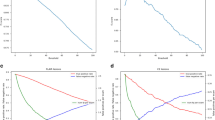

A 3D CNN with a U-Net like encoder–decoder architecture (Fig. 1) was externally developed by jung diagnostics GmbH, Hamburg, Germany, and provided for external validation on our dataset.

Architecture of the externally developed and trained 3D CNN with a fully convolutional encoder–decoder architecture with 3D convolutions, residual-block connections and four reductions of the feature map size. The two input images (T1-weighted post-contrast patch and registered FLAIR patch) were fed into the same encoder path with shared weights. Following every residual-block, the feature maps for the T1-weighted and the FLAIR input were concatenated and fed into the decoder. A segmentation mask was predicted, indicating contrast-enhancing lesions and background classes (grey matter, white matter, cerebrospinal fluid and FLAIR lesions). CNN, convolutional neural network; FLAIR, fluid-attenuated inversion recovery

For the DL framework, the heterogeneous input scans were re-sampled into an isometric 1 mm × 1 mm × 1 mm 3D-space and fed into the encoder in zero mean unit variance 160 × 160 × 160 patches. A rigid registration was used to register the corresponding FLAIR on the T1-weighted images beforehand. Information from FLAIR images was included in order to enhance network performance and reduce false positive rate. The two input patches were fed into the same encoder path with shared weights. Following every residual-block, the feature maps for the T1-weighted and the FLAIR input were concatenated and fed into the decoder. The encoder–decoder structure used was fully convolutional with 3 × 3 × 3 kernel size 3D convolutions. Four blocks with residual-block-connections reduced the spatial feature map four-times in the encoder path, before they got up-sampled to the original patch-size by the decoder. The output was six 3D probability masks at the same size as the original image, one for each segmentation that has been trained (CE lesions, FLAIR lesions, grey matter, white matter, cerebrospinal fluid, background). After the training, the final 3D CNN was transferred to the clinical institution which was responsible for the validation. Of note, the institution was not involved in the development and training phase and the training data did not include any scans from the MRI scanner used for testing.